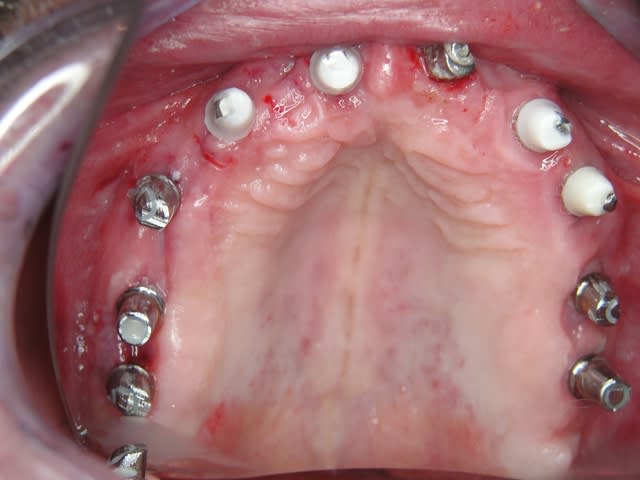

Un cas qui va sans doute prêter à discussions, juste pour montrer que la technique MIMI (non invasive) peut donner des résultats de qualité et esthétiques en moins de temps qu une chirurgie dite traditionnelle.

Les deux premières photos montrent le cas d´une jeune femme ( qui malheureusement s est fait retiré toutes les dents à l´étranger....).Ce cas a pu être terminé deux semaines après l´implantation.

Je sais bien que 8 implants auraient suffit cependant 10 ont été posés.Nous voulions remplacer chaque racine avec un implant.

Le patient n a jamais eu de problèmes ( juste avec une hygiène buccale normale, brosse à dents).

Les deux dernières photos montrent le même cas deux ans plus tard.

Ça me fascine de te voir poser 10 implants en flapless à la mandibule sans guide ici, et réussir. On pourra discuter la méthode, mais pas la main du chirurgien. Bravo.

Mon guide était l´ancienne prothèse avec laquelle j´ai fait un OPG en plaçant un trombone metallique entre les dents 4 et 5 dans la prothèse, ainsi j ai pu utiliser la prothèse comme un guide pour éviter un problème avec la zone foraminale....